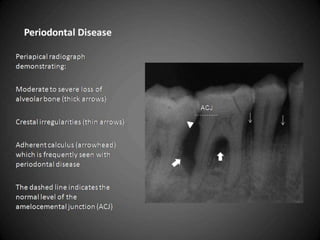

   Examination of bone:

   Height of alveolar bone

   Crest relative to teeth

   Loss of height-more than 1.5 mm-periodontal

disease

   Cortication

   Lamina dura + PDL space + tooth roots

   Carcinoma-erosion of alveolar crest+ ill defined

borders.